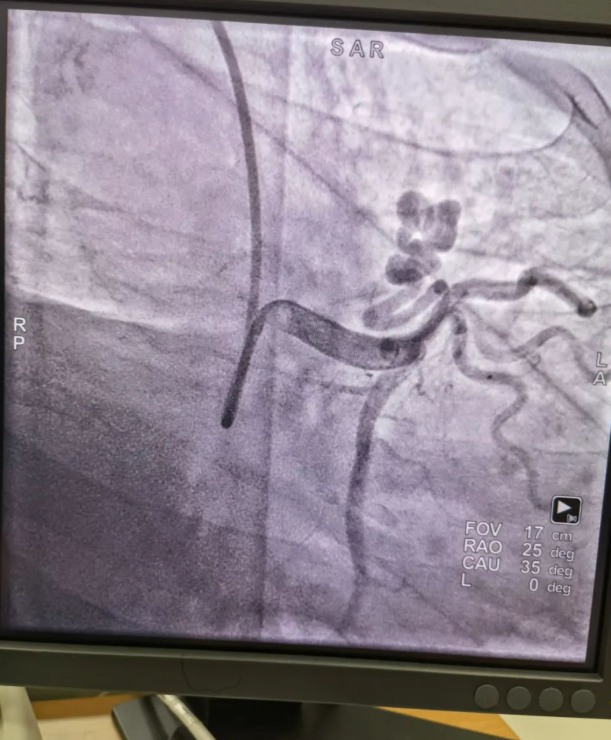

不久前,來自新疆的患者石先生去年至今反復(fù)胸悶、氣短、胸痛,就診于新疆某院,懷疑“冠心病”,住院行冠狀動脈造影術(shù),石先生造影提示“冠狀動脈肺動脈瘺”,而他并非“冠心病”,所以給予的“冠心病”治療,效果不佳。出院后仍反復(fù)出現(xiàn)胸痛、胸悶、氣短等癥狀,經(jīng)親友介紹了解到西安國際醫(yī)學(xué)中心醫(yī)院心臟病醫(yī)院心臟內(nèi)科二病區(qū)曾廣偉主任,多年來潛心研究心臟病介入治療,成功主刀救治了許許多多高危復(fù)雜病例,尤其是在先心病及結(jié)構(gòu)性心臟病封堵,以及冠心病、心律失常射頻消融及起搏治療等方面積累了豐富的診療經(jīng)驗。

此病例罕見,在曾廣偉從醫(yī)18年生涯里曾碰到有2個印象深刻的病例,患者分別是53歲和66歲,當(dāng)時建議患者入院進行動脈瘺的封堵術(shù),但患者和家屬考慮到這個手術(shù)案例極少,風(fēng)險也高,均未接受手術(shù)治療建議,只是能采取藥物保守治療,出院后隨訪得知患者癥狀緩解效果不佳,后來在隨訪中也與53歲患者失去了聯(lián)系,而66歲患者因冠狀動脈肺動脈瘺出現(xiàn)反復(fù)心衰,在當(dāng)?shù)蒯t(yī)院藥物治療,短短2年時間,患者因為動脈瘺未及時手術(shù)失去了生命。所以此次患者石先生到訪,曾廣偉主任在詳細掌握病例資料基礎(chǔ)上,果斷建議進行動脈瘺的封堵術(shù)治療,為了提高手術(shù)成功率和精準(zhǔn)度,曾廣偉主任搜集相關(guān)診療資料,反復(fù)推演論證,經(jīng)過相當(dāng)充足的準(zhǔn)備工作,于5月18日成功進行了封堵手術(shù),完全堵上了瘺口。

患者術(shù)后第2天,已經(jīng)沒有明顯的胸悶、氣短、胸痛等癥狀,目前身體狀態(tài)良好。本次手術(shù)曾廣偉主任及其團隊,采取從右手臂一根血管進入,并在2小時之內(nèi)完美封堵,創(chuàng)口小,痛苦小。手術(shù)雖然難度大、風(fēng)險高,相關(guān)案例也少,但是曾廣偉主任主刀即在巔峰,這樣一臺完美的手術(shù)靠的不是運氣,是豐富的臨床手術(shù)經(jīng)驗,扎實的專業(yè)知識儲備,以及對醫(yī)療事業(yè)的孜孜追求。

冠狀動脈瘺是指冠狀動脈與心腔、冠狀靜脈、肺動脈等的異常連接,是一種少見的先天性心臟病,發(fā)病率為1.3%。而冠狀動脈肺動脈瘺是冠狀動脈與肺動脈之間產(chǎn)生的一種血管性瘺口,導(dǎo)致冠狀動脈里的血液流入肺動脈里,使冠狀動脈里血液流量減少,出現(xiàn)心肌供血不足,冠狀動脈肺動脈瘺會使患者出現(xiàn)胸部疼痛、胸悶、呼吸困難、頭暈、乏力等一系列癥狀,隨著疾病不斷進展,可引發(fā)心功能的障礙和心肌缺血,肺動脈會逐漸形成肺動脈高壓,還可能導(dǎo)致動脈瘤的破裂,甚至威脅病人的生命安全,所以早期發(fā)現(xiàn)和治療冠狀動脈肺動脈瘺,對病人的預(yù)后改善具有重要的意義。